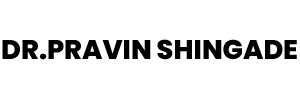

Endoscopy

Diagnostic and therapeutic endoscopic procedures that help identify and manage digestive system concerns.

- Endoscopic diagnostic and therapeutic procedures